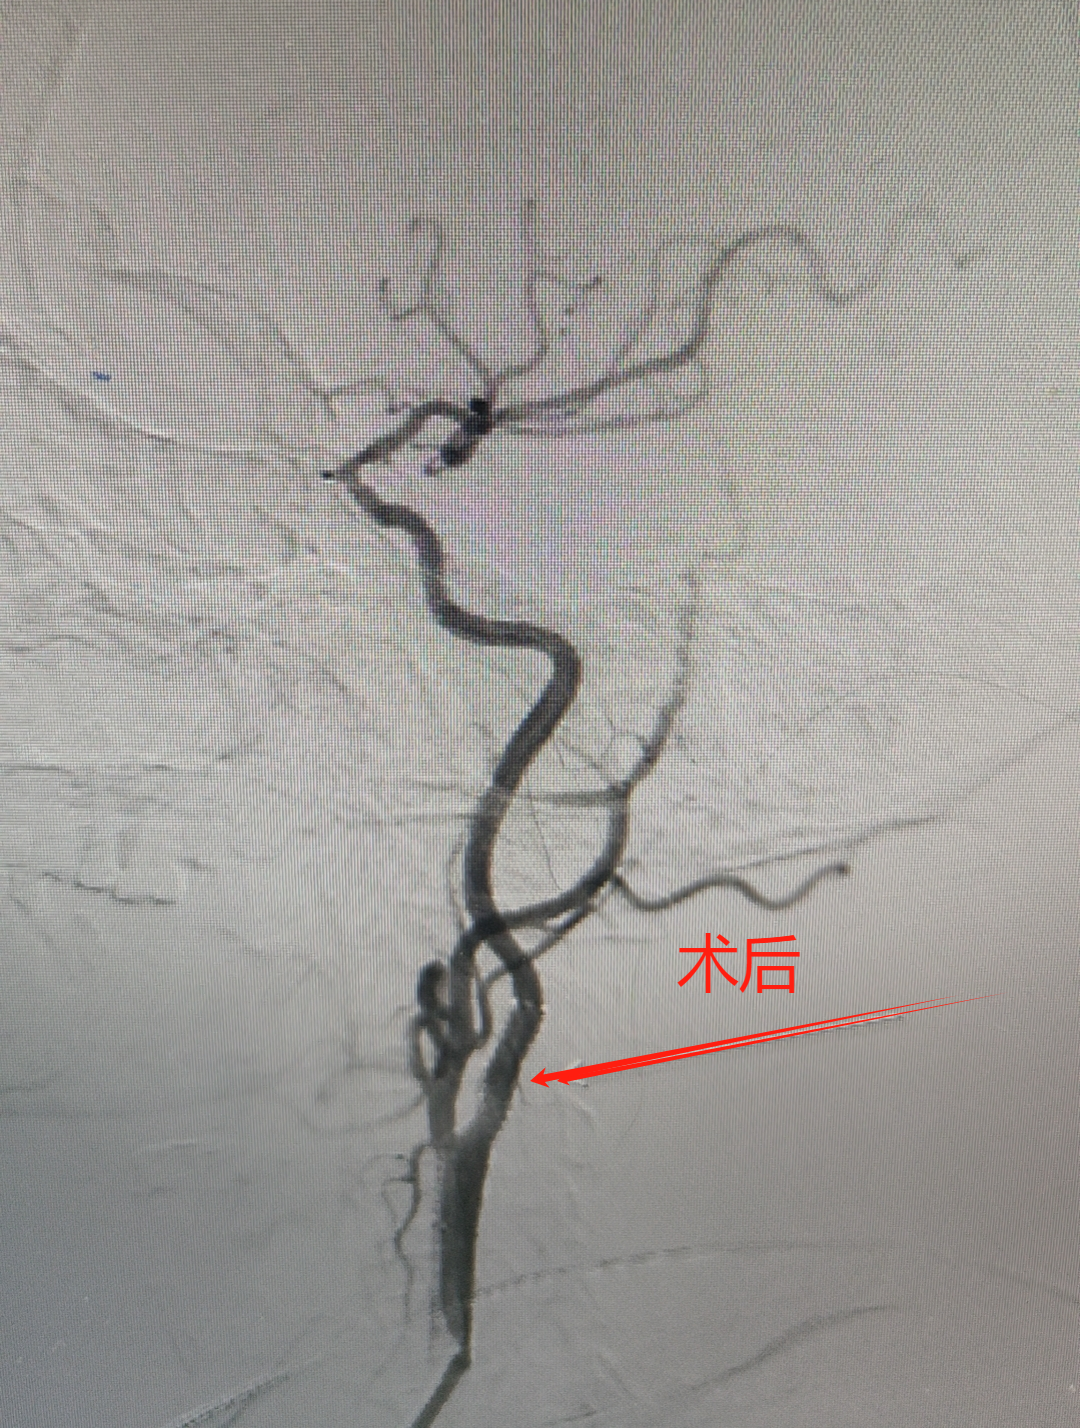

73岁王阿姨突发言语不清、说话费力,伴左侧肢体无力,持物不稳,口角歪斜。入院后经检查为急性脑梗塞,随时有猝死的风险。5分钟急诊介入取栓治疗后,效果立竿见影,当即言语清晰,左侧肢体能平稳上抬。

61岁刘大爷记忆力下降,反应大不如前且肢体乏力,经颈血管超声检查发现颈动脉重度狭窄。神经内科介入团队为其植入支架开通了狭窄的血管。术后,患者头晕、肢体乏力及反应、记忆力等情况逐渐好转。